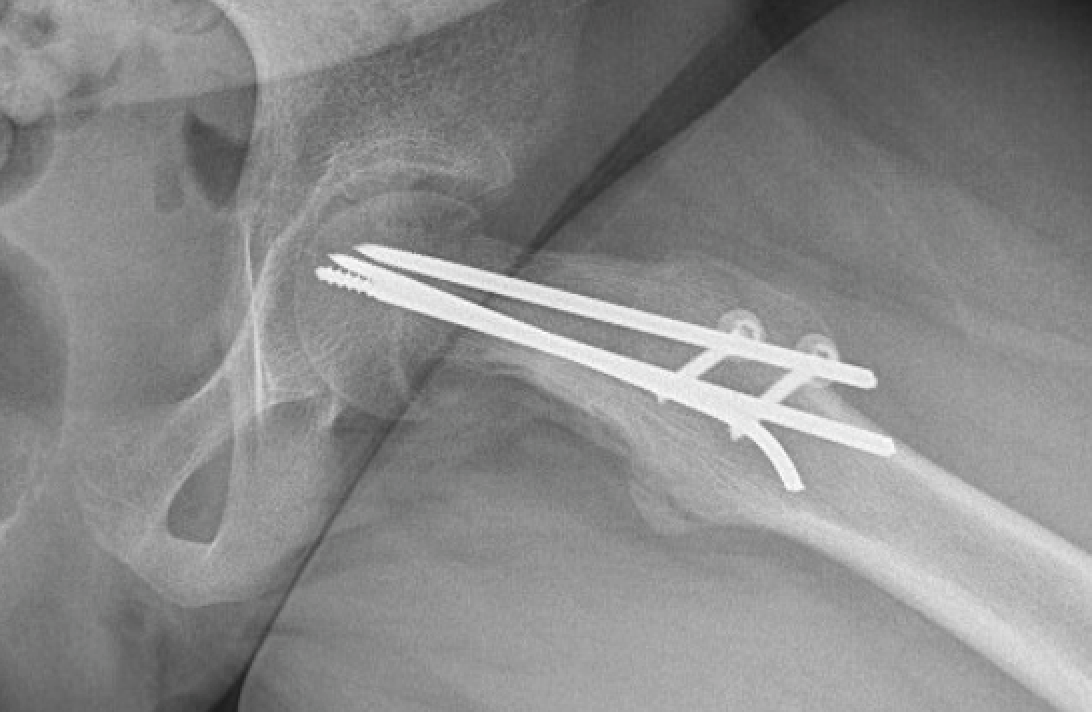

Als de verplaatsing toch groot is dan zal de heupkop chirurgisch terug op de goede plaats gezet worden en eveneens gefixeerd worden met 3 pinnen. De ingreep gebeurt via een surgical dislocation.